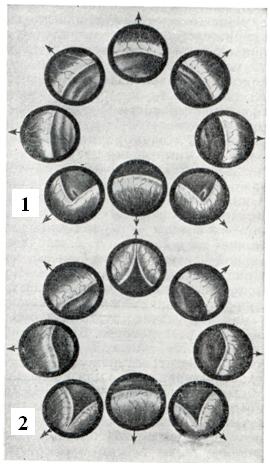

В предстательной железе в практическом отношении принято различать: верхнюю, или переднюю, — краниальную часть и нижнюю, или заднюю,— каудальную часть; с возрастом различие строения этих частей выявляется отчетливее (рис. 1 и 2).

Аденома развивается в краниальной части, а рак — в каудальной. Аденома и рак предстательной железы могут сосуществовать у одного и того же больного одновременно.